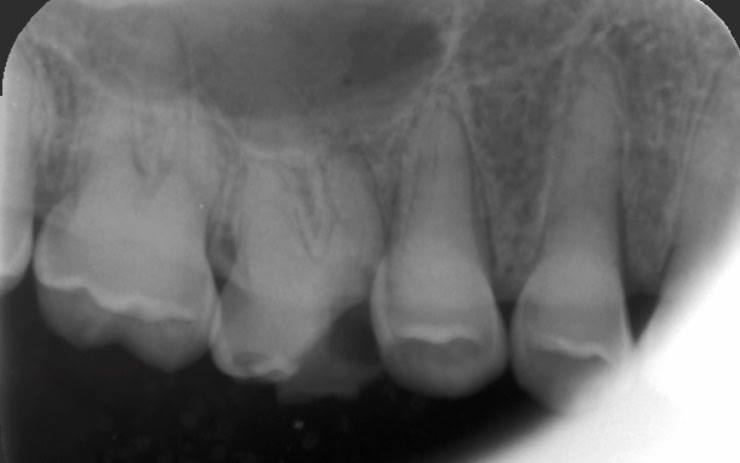

Radio 16

781774c1 a8e8 49b4 8faa 683eca2bb0a4 u2c9ob - Eugenol

poignée de porte a diagnostiqué une maladie genetique, c'est un cas d'amélogenèse imparfaite avec racines courtes, obliteration des chambres pulpaires, émail fin et de mauvaise minéralité pour du collage... necrose en lien avec l'usure (les incisives inf)

il faudrait donc faire des élongations maousses , mais comme les racines sont courtes , ce sera des implants .

Et oui implants sur tout le secteur antérieur + 46 et 36 avec un petit rabotage de 12 à 22. Plus couronnes sur 16 et 26 et sur d’autres pour refaire les courbes . Et pas de changement de DVO effectivement comme le montrent ses PM et ce qu’ a dit Enlaye.